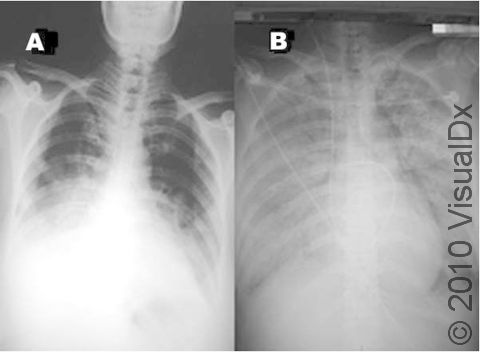

More severe symptoms include:

- Pneumonia

- Respiratory failure